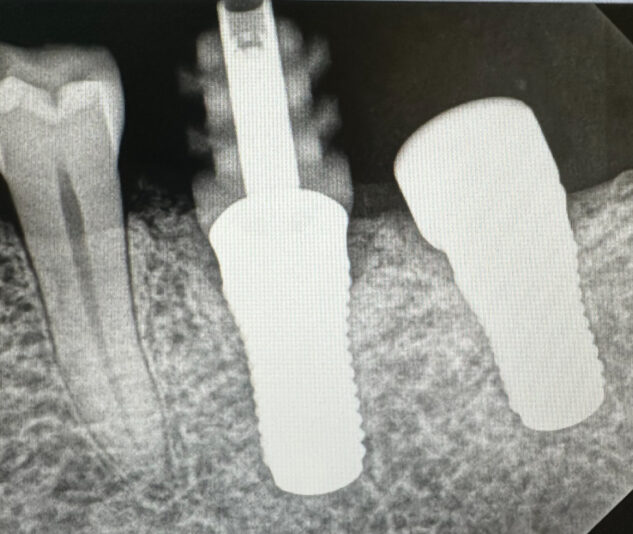

This healing cap was in place for 5 months. I couldn’t get it out through conventional means, and stripped the threads trying.

Then I had the brilliant idea to review the radiograph, and it appears to be bent?

But physics is telling me this isnt going to back out if it’s bent.

The system is Straumann.